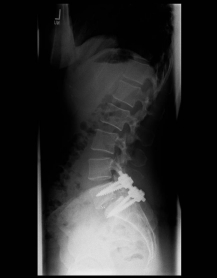

Spondylolisthese ISpondylolisthese II

X-ray image of a slipped vertebra in the lower lumbar spine before and after surgery